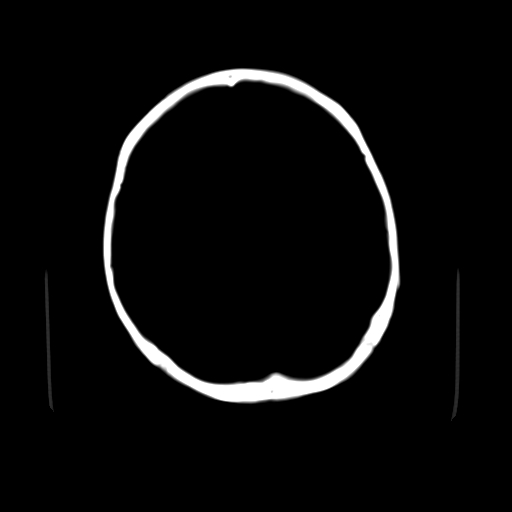

颅内未见明显异常,枕骨松质骨瘤可能性大。颅骨板障起源骨瘤较常见,骨血管瘤有垂直骨针及粗大钙化,嗜酸性肉芽肿软组织有改变,典型者可见“纽扣状”死骨,年龄通常较小。

枕骨松质骨良性病变。

左枕骨松质骨不均匀低密度灶,边缘清楚,考虑良性松质骨性骨瘤可能性大。